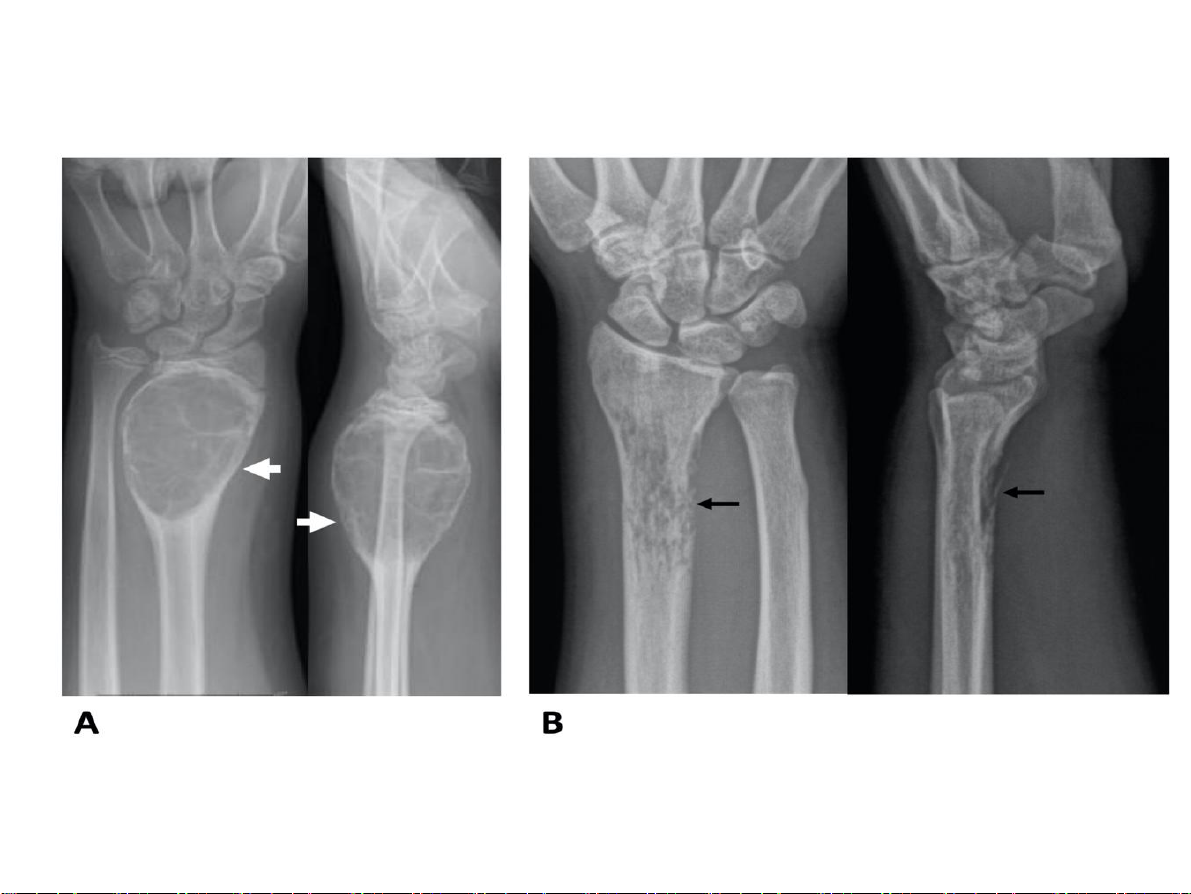

Bất thường về cấu trúc Huỷ xương 1.Giới hạn tổn thương

• Không rõ, vùng chuyển tiếp

rộng tổn thương tiến triển nhanh

• Rõ, vùng chuyển tiếp hẹp lành tính 31-Jan-23 CĐHA Cơ-Xương-Khớp

• Không rõ, vùng chuyển

tiếp rộng tổn thương tiến triển nhanh

• Rõ, vùng chuyển tiếp hẹp lành tính. 31-Jan-23 CĐHA Cơ-Xương-Khớp Huỷ xương 31-Jan-23 CĐHA Cơ-Xương-Khớp Huỷ xương 31-Jan-23 CĐHA Cơ-Xương-Khớp 31-Jan-23 CĐHA Cơ-Xương-Khớp